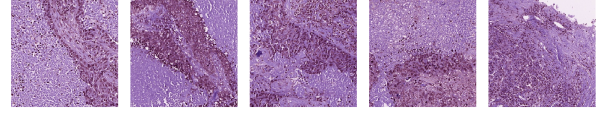

| Cluster 15 ( |

![]() |

| Cluster 34 ( |

| Cluster 23 ( |

| Cluster 43 () |